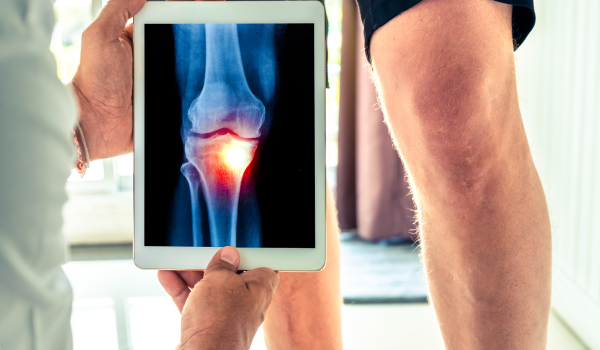

Both OA and RA require a combination of:

Physical exams

Medical history review

Imaging tests (X-rays or MRI scans)

However, RA diagnosis often includes blood tests to check for markers like rheumatoid factor (RF) or anti-CCP antibodies, which indicate immune system activity.